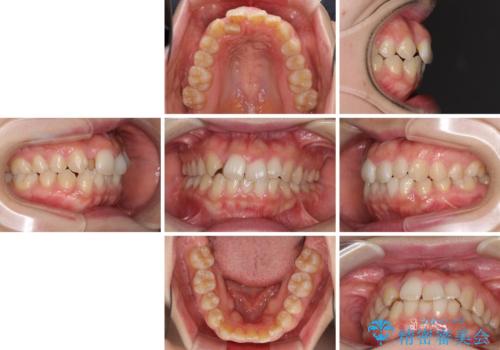

- 右上の八重歯と、左下八重歯を抜いてしまったことを気にして来院された患者様です。

下顎は既に犬歯を1本抜歯しているため、上顎右側第一小臼歯を抜歯し、ワイヤー装置にて歯列を整えることとしました。

変則的な抜歯となるため、正中と人中がずれる可能性がありましたが、仕上がりは上下正中を揃えることができました。